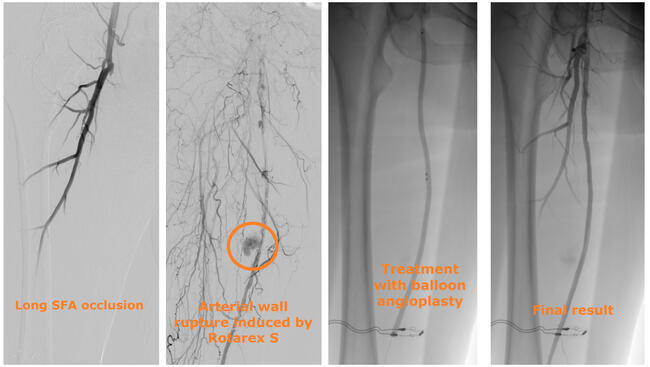

A 44-year-old man presented with chronic limb-threatening ischemia. He had rest pain and first-toe necrosis (Rutherford classification stage 5). Computed tomography angiography (CTA) highlighted thrombosis of a femoropopliteal venous bypass that was performed more than 2 years earlier. An atherothrombectomy device was used to recanalize the bypass (Figure 1). The procedure was complicated by bypass rupture and acute hemorrhage. A 5-mm x 50-mm Viabahn self-expandable covered stent (Gore) was promptly deployed to successfully stop the bleeding.

Abbreviations: DFA, deep femoral artery; SFA, superficial femoral artery.

When an arterial wall rupture induced by atherectomy occurs, the treatment is driven by the rupture characteristics; our treatment algorithm is shown in Figure 3. When the perforation is not associated with bleeding or is associated with low-flow bleeding, prolonged balloon angioplasty is typically sufficient. When the rupture is associated with high-flow bleeding, prompt deployment of a self-expandable covered stent is indicated.